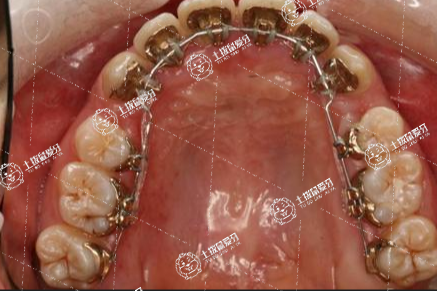

牙齒太稀疏要矯正牙齒,整理牙齒排列,制作平弓,矯正牙齒,閉上接縫,分散在縫隙中,集中在牙齒缺損的部位,接受修復治療,通過義齒鑲嵌的方式解決缺失的牙齒。在正畸治療期間,齲齒和牙周病經(jīng)常發(fā)生,因為不容易保持口腔衛(wèi)生,所以建議在正規(guī)醫(yī)院口腔科拍攝牙齒,確定矯正治療方案。

牙齒太稀疏,首先要看是否有牙齒卡在骨中,如果薄膜顯示有保留的牙齒,可以分析是否可以做正畸牽引,正畸牽引與整口矯正,可以恢復正常的牙形。如果里面沒有牙胚,缺牙,那么牙齒可以先正畸,然后在缺牙之間留下間隙,矯正結(jié)束后再植入,這樣也可以恢復完整的牙列形態(tài)。如果沒有牙齒保持本身,沒有牙齒丟失,那么直接糾正就可以了。

牙齒很稀,一般都能矯正好。要到口腔科就診,醫(yī)生通過臨床檢查,借助拍片檢查,了解牙齒稀疏的原因,然后進行相應的處理。如果牙齒稀疏是因為鄰牙擁擠造成的,可能可以進行正畸治療,來矯正牙齒稀疏的問題。如果牙齒稀,是因為牙齒發(fā)育不好,過小牙,造成兩個牙齒之間縫隙很大,可以通過做牙齒的貼面修復,或者是烤瓷冠修復,來矯正牙齒稀疏的問題。如果是因為先天性缺失恒牙,造成牙齒稀疏,要通過修復治療矯正牙齒稀疏,可以是活動修復、烤瓷橋修復,或者是種植修復。如果是因為骨頭發(fā)育異常,造成牙齒稀疏,可能要到口腔外科,作正頜手術矯正。